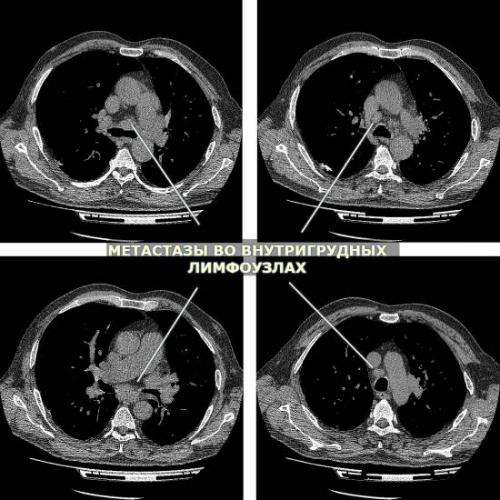

Как выглядят метастазы в легком на КТ?

Метастазы в легких на КТ Лимфогенные метастазы легких на КТ выглядят как множественные мелкие диссеминированные очаги. Они расположены вдоль междольковых перегородок и плевры. Картина напоминает туберкулез и саркоидоз, и в этой связи часто требует уточнения.